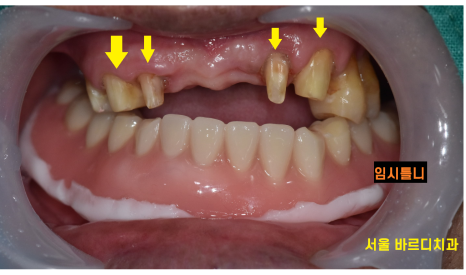

한눈에 보아도 군데군데 썩어있고...

이미 뽑힌 치아도 많았습니다.

치아 상실로 인하여 잇몸 수축이 진행되어 실제보다

나이가 들어보이는 인상을 가지고 계셨는데요.

뽑힌 치아도 많았고

앞으로 뽑아야 할 치아도 많았습니다.

상악은 그나마 괜찮았지만

아래 치아 같은 경우 하악 전체 임플란트가 필요했습니다. '